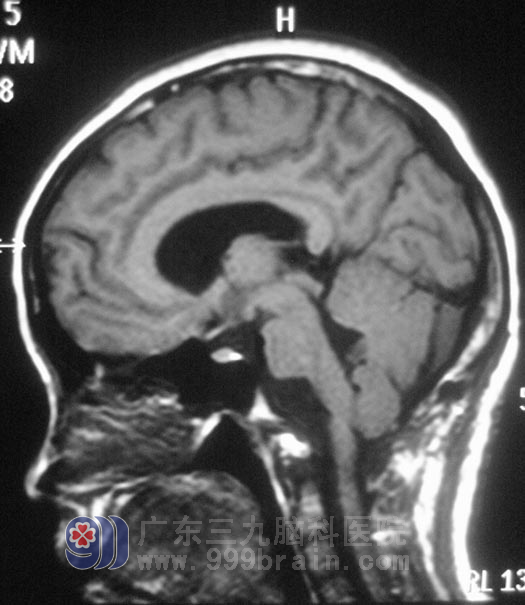

12月13日,鲁明主任主刀,在全麻下行右侧延髓腹外侧胆脂瘤切除术,作“倒L”型切口,术中见灰褐色肿瘤组织,位于右侧延髓腹外侧,质软,血供一般,在显微镜下分块切除,肿瘤基底部与副神经、舌咽神经、迷走神经粘连紧密,予镜下小心分离后切除,对副神经、舌咽神经、迷走神经、小脑后下动脉均保留完整,手术过程顺利。经过一段时间的治疗,小凤没有出现术前担心的并发症,术前症状均有所缓解。术后经病理证实为:(延髓腹外侧)胆脂瘤。